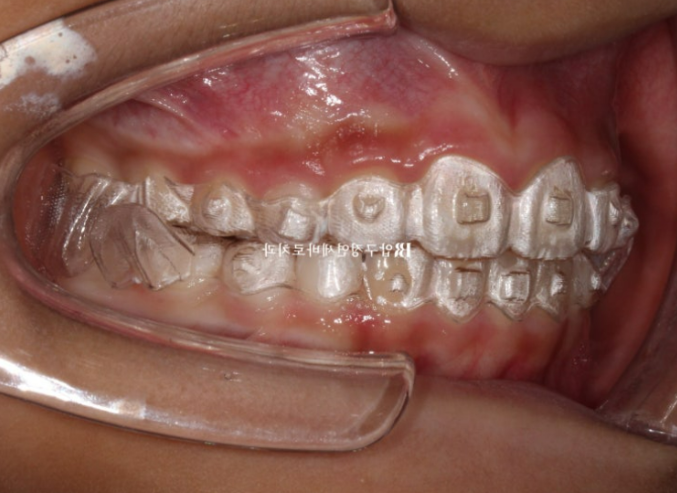

23.09

실제로 입안에서는 이렇게 구현이 됩니다.

아래턱을 내밀어서 물지 않으면 윙끼리 간섭때문에 입이 다물리지 않습니다.

앞에서 보면 이런 모습입니다.